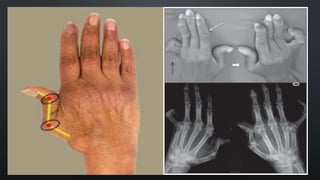

This document references several articles on rheumatology from 2011 and 2013. It discusses deformity without erosion in rheumatology patients, based on articles from Santiago and Lopez Longo. Key topics covered include diagnostic criteria for rheumatoid arthritis and outcomes for patients experiencing deformities without joint erosion.